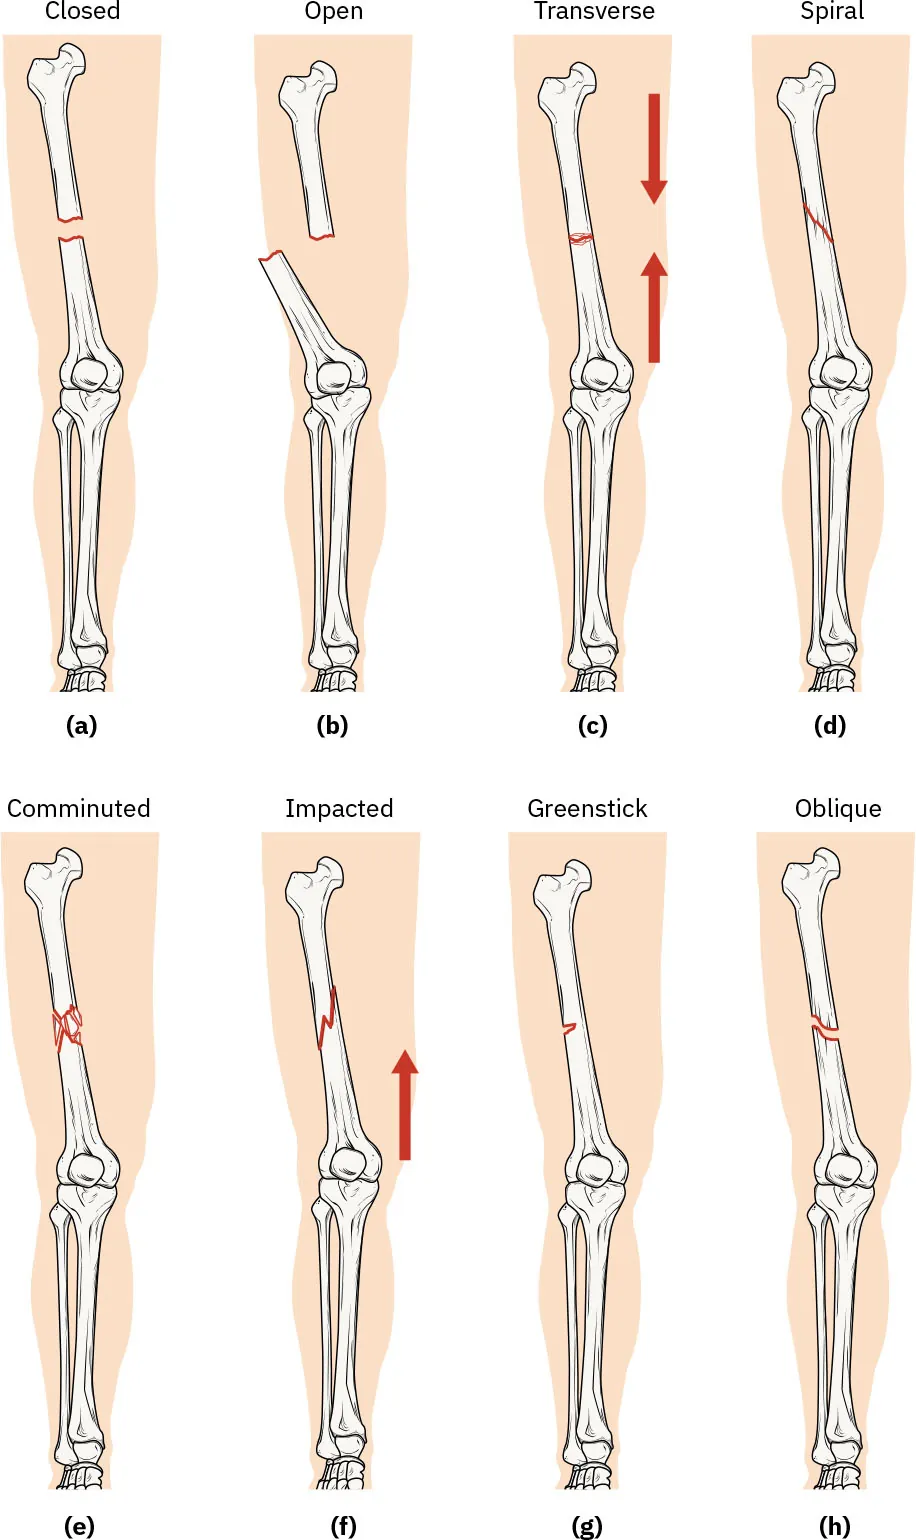

Fractures are classified by their complexity, location, and other features (Figure 13.10; Table 13.3). Some fractures have the features of more than one type of fracture and therefore may be described using more than one term (e.g., an open transverse fracture).

Diagrams of leg bones showing (a) closed fracture, (b) open fracture, (c) transverse fracture, (d) spiral fracture, (e) comminuted fracture, (f) impacted fracture, (g) greenstick fracture, and (h) oblique fracture

Figure 13.10 There are several types of fractures: (a) closed fracture, (b) open fracture, (c) transverse fracture, (d) spiral fracture, (e) comminuted fracture, (f) impacted fracture, (g) greenstick fracture, and (h) oblique fracture. (credit: modification of work from Anatomy and Physiology, 2e. attribution: Copyright Rice University, OpenStax, under CC BY 4.0 license)

Type of Fracture Description

Closed (or simple) Fracture in which the skin remains intact

Comminuted Fracture with several breaks, resulting in many small pieces between two large segments

Greenstick Partial fracture in which only one side of the bone is broken

Impacted Fracture in which one fragment is driven into the other, usually as a result of compression

Oblique Fracture that occurs at an angle that is not 90 degrees

Open (or compound) Fracture in which at least one end of the broken bone tears through the skin; carries a high risk of infection

Spiral Fracture in which bone segments are pulled apart by a twisting motion

Transverse Fracture that occurs straight across the long axis of the bone

Table 13.3 Types of Fractures